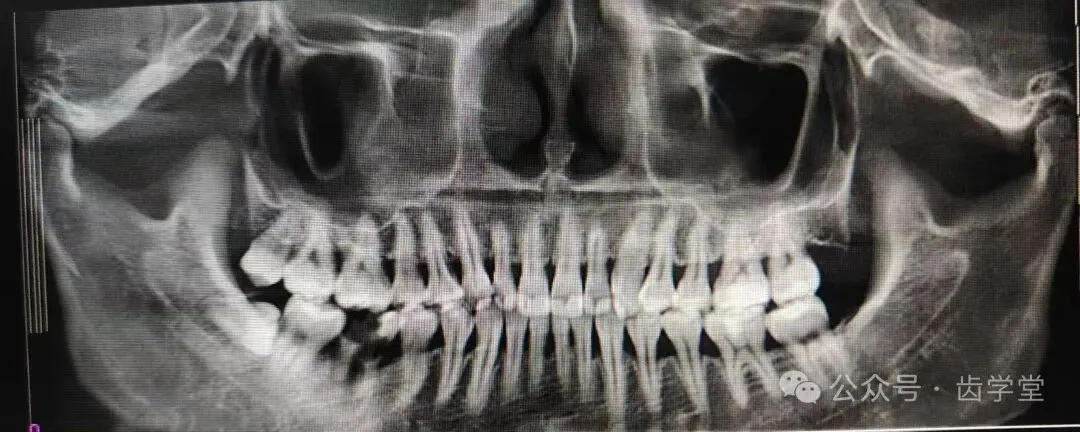

5. 自体牙移植的适应症和禁忌症及其把控;

8. 自体牙移植的术前检查、评估和准备;

9. 自体移植供牙选择原则;

13.受植位点不同情况移植的区别及其要点;